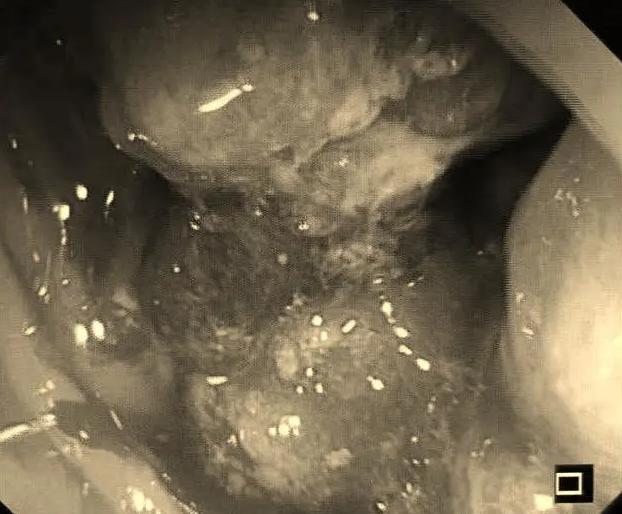

距肛门10-12cm处,一个巨大环周性占位!直肠癌,而且应该是晚期!

巨大占位性病变